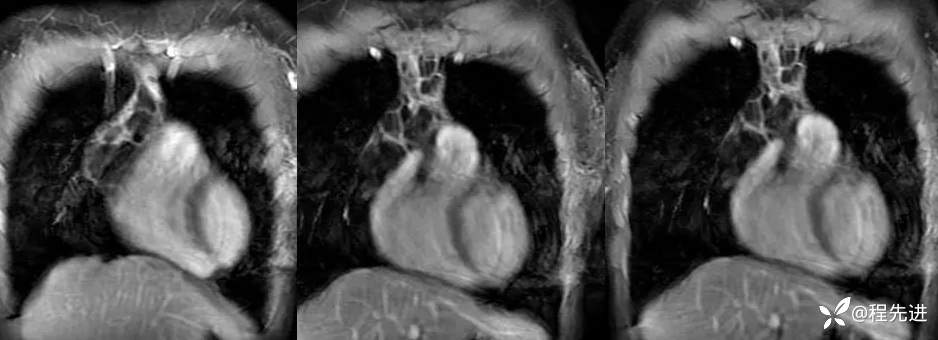

增强